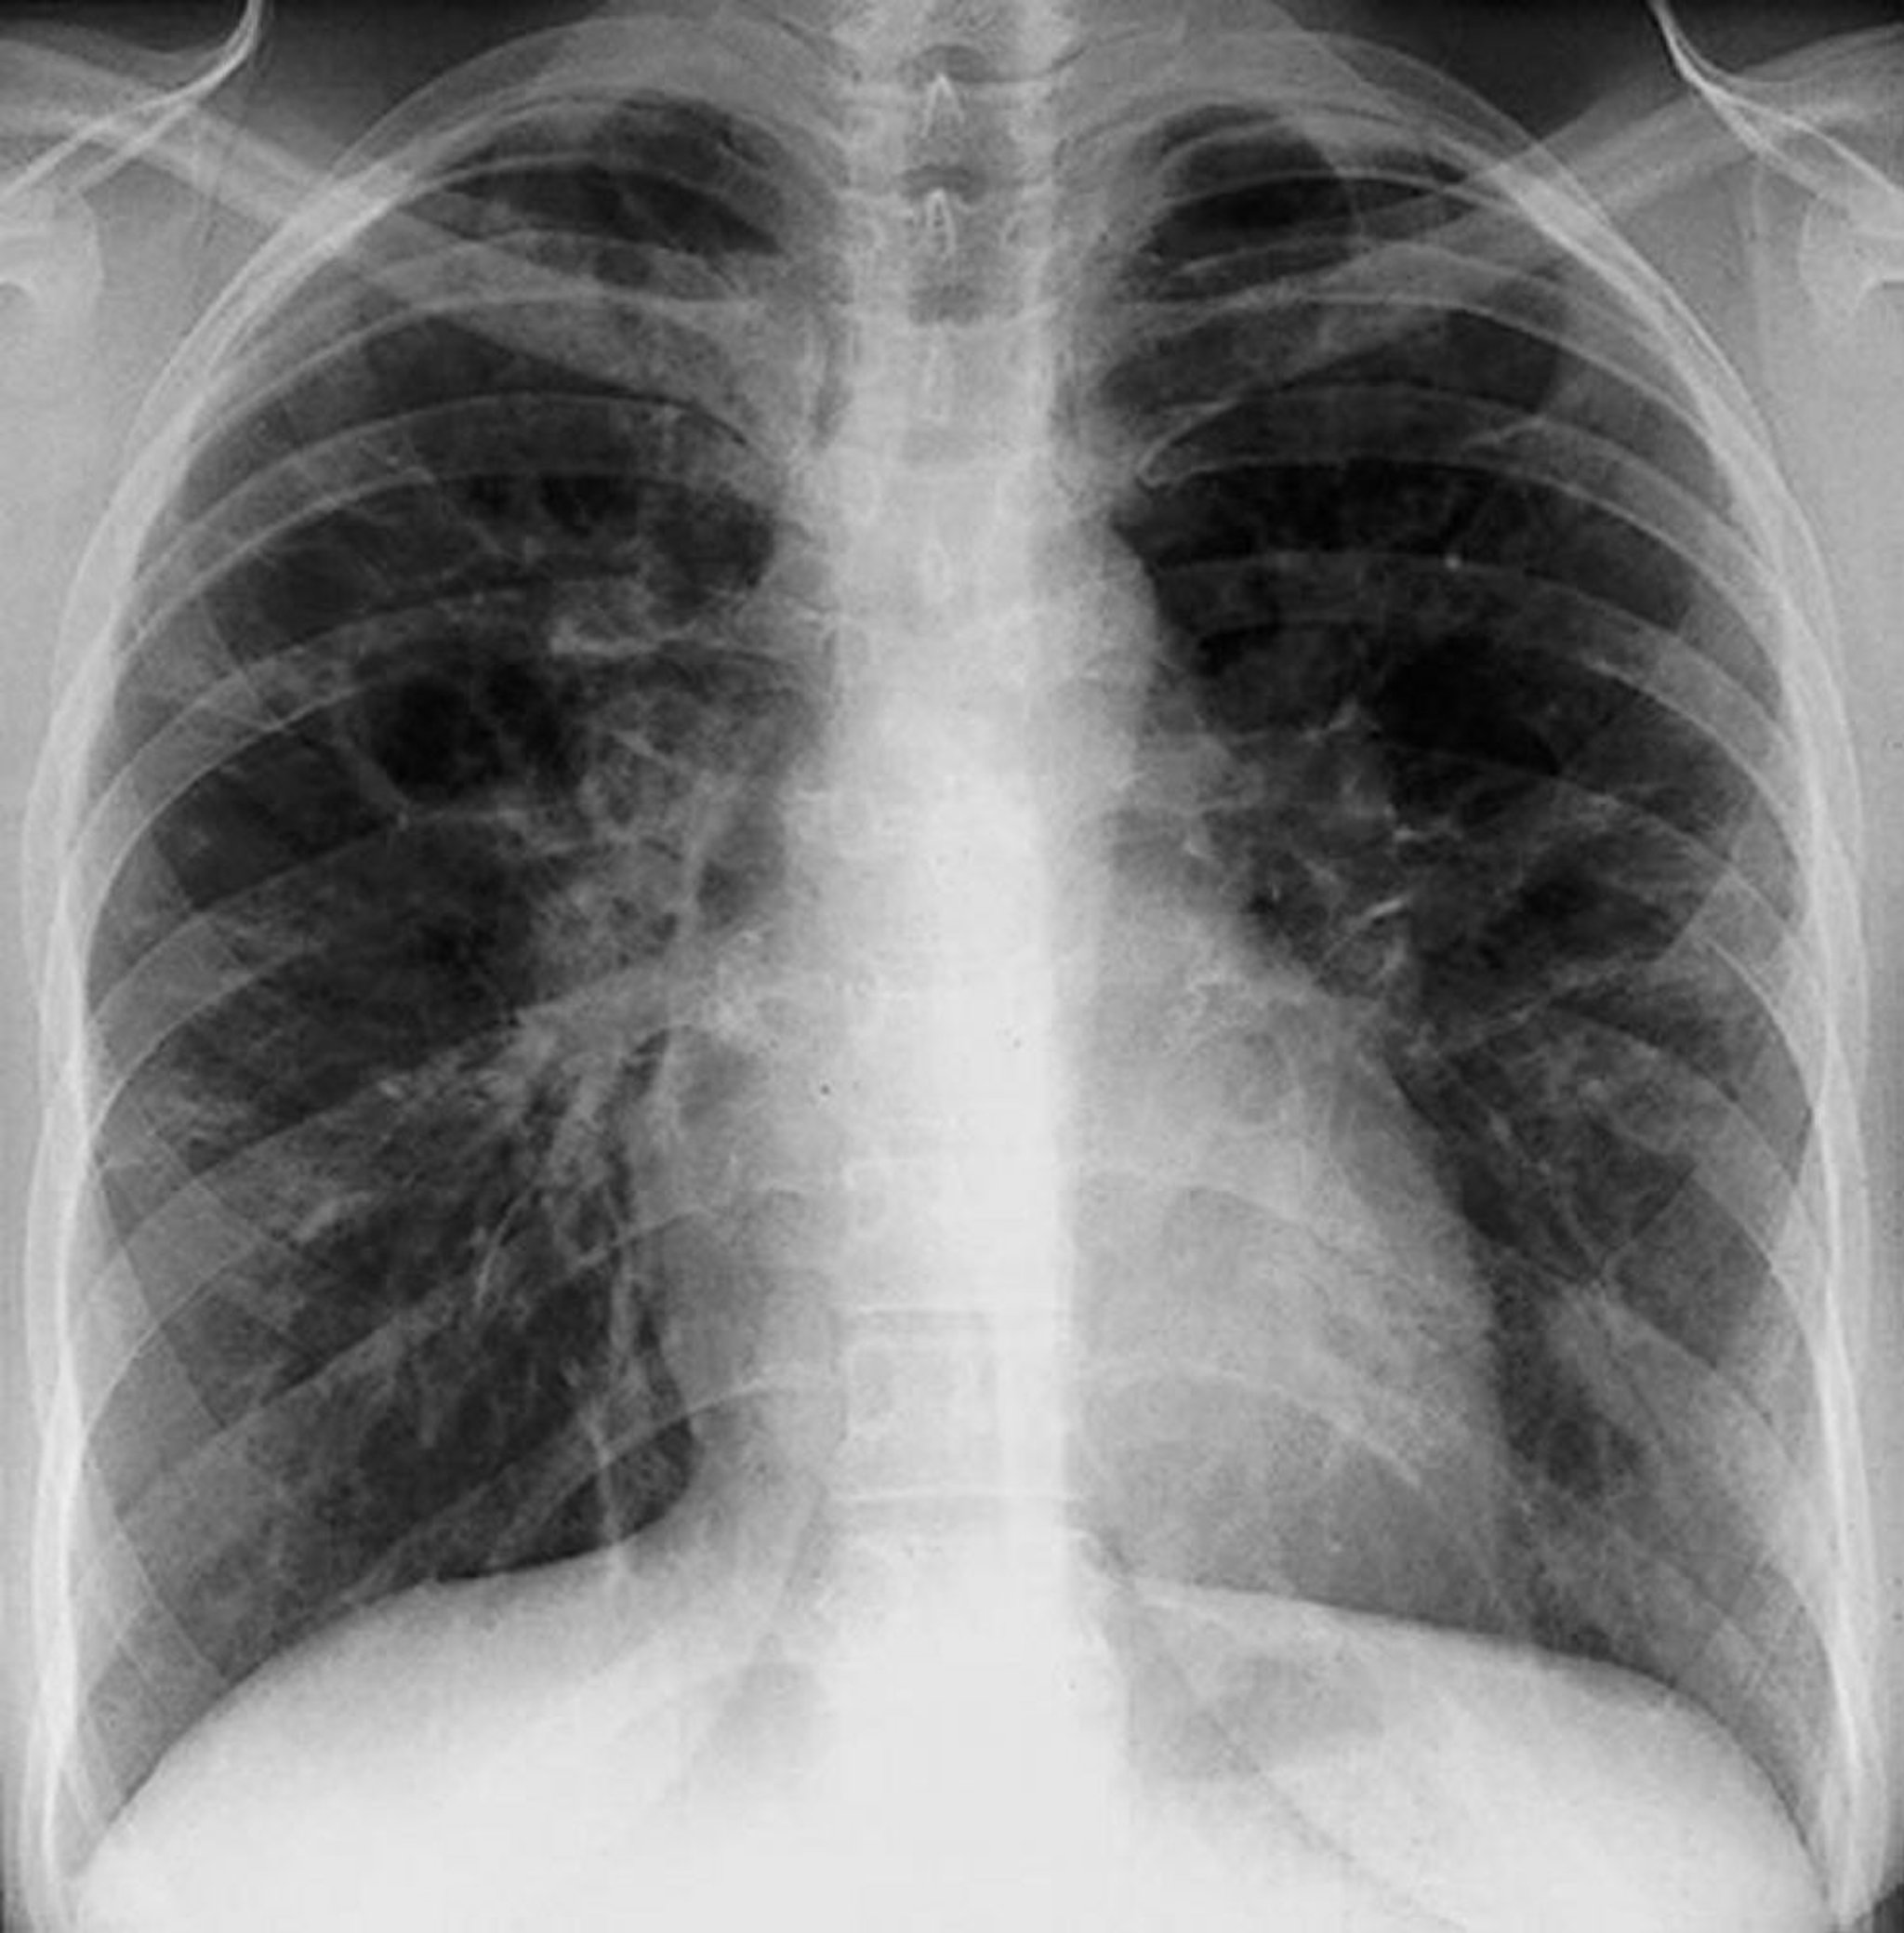

Sarkoidose (Stadium III)

Diffuse interstitielle Trübungen ohne hiläre Adenopathie bei Sarkoidose im Stadium III.

By permission of the publisher. Aus Tanoue L, Elias J. In Bone's Atlas of Pulmonary and Critical Care Medicine. Edited by J Crapo. Philadelphia, Current Medicine, 2005.